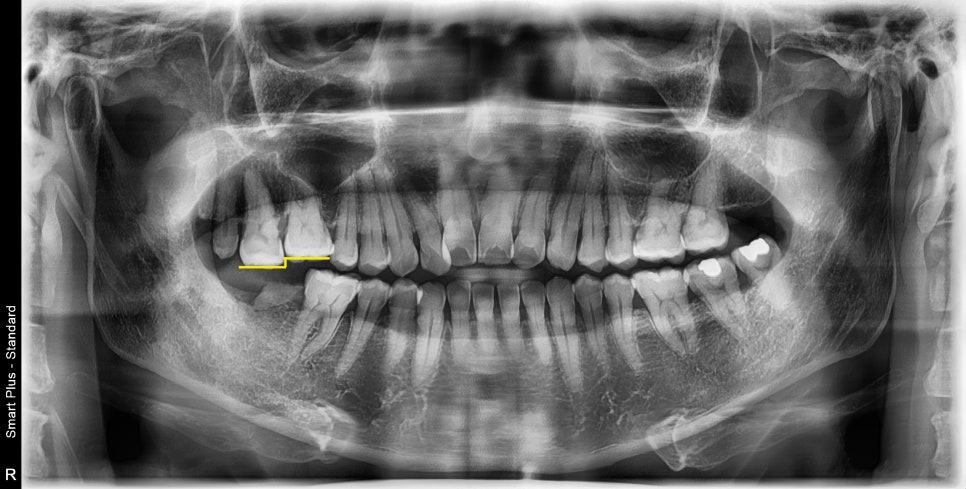

과거에 치아머리 부분이 부러졌을 때 치료 없이

뿌리만 남은 상태로 오랜 시간 지난 케이스입니다.

최후방 어금니 한 개가 상실되었는데

발치하고 임플란트 설명을 들으시고 두려움에 치료를 미루셨다고 하셨습니다.

사진에서 보듯이 지지해 주는 아래 치아가 상실되었기 때문에

시간이 지남에 따라 대합 되는 치아가 밑으로 정출되었습니다.

치아의 높이가 계단처럼 되어있습니다.

정출되는 양이 적고, 공간이 충분한 경우는 해당 치아를 건드리지 않고 임플란트만 진행하지만

위 환자분 같은 경우는 임플란트가 들어갈 공간 자체가 나오지 않을 만큼

치아가 정출되었기 때문에 의도적으로 크라운 치료가 필요한 케이스입니다.